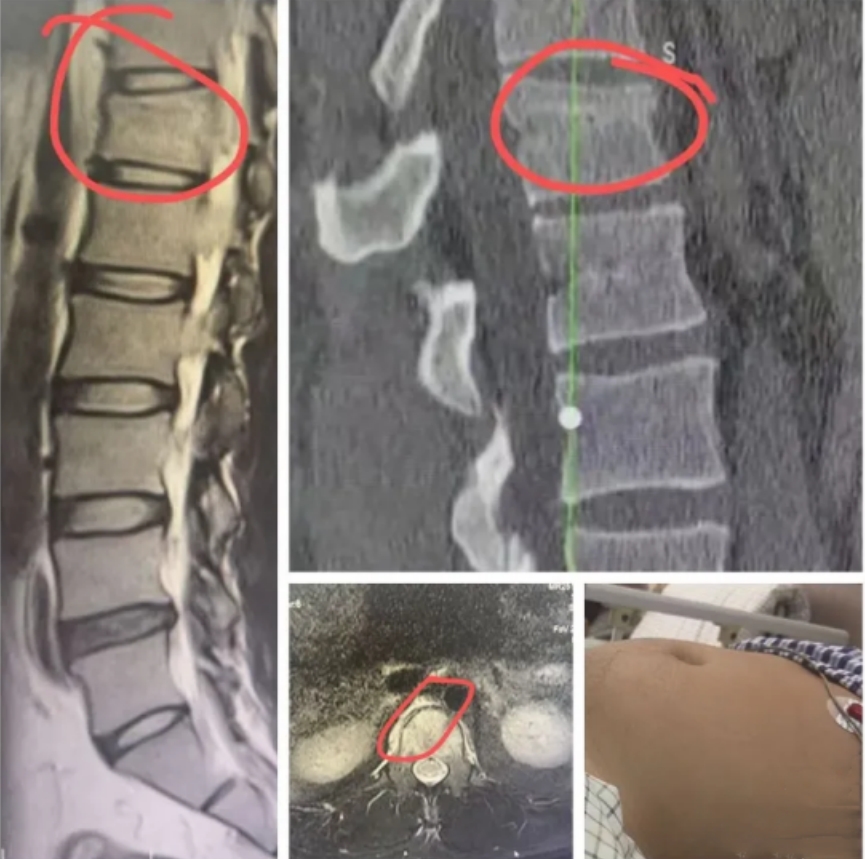

(▲术前影像资料)

入院后,完善相关检查显示:脊柱椎体前中柱压缩爆裂骨折,椎体出血伴随腹膜后血肿;更危险的是,血肿压迫腹丛神经已引发麻痹性肠梗阻。小伙子腹部胀大如鼓,无法排气排便,每一分钟的延误都可能造成严重的后果。